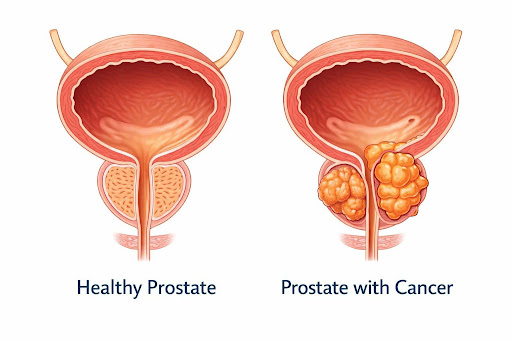

Overview: What is Prostate Cancer?

Prostate cancer occurs when certain cells in the prostate gland begin to grow abnormally and uncontrollably. The prostate is a small gland found only in men, responsible for producing seminal fluid that helps transport sperm.

In many individuals, prostate cancer progresses slowly and may remain confined to the prostate for years.

In some cases, cancer can grow more actively and spread to other parts of the body if not detected and treated early.

How It Develops

Prostate cancer develops when some prostate cells acquire damage that disrupts normal growth.

These cells multiply uncontrollably and live longer than normal cells, forming a growth in the prostate

Prostate adenocarcinoma – arises from fluid-producing glandular cells

Rare subtypes exist but are uncommon

These cells multiply uncontrollably and live longer than normal cells, forming a growth in the prostate

- Often slow-growing and confined to the gland

- Can become aggressive and spread to lymph nodes or bones over time

Prostate adenocarcinoma – arises from fluid-producing glandular cells